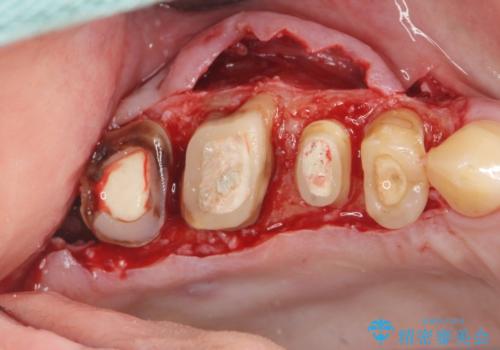

根管治療・歯周外科を行い歯を残した、複合的虫歯治療

検査の結果、根管・クリアランス・虫歯といった複合的な問題が認められ、以下のような治療計画を進めることとしました。

根尖病変 →マイクロスコープを用いた精密根管治療の実施

クラウンの製作スペースの付属 →歯周外科によるスペースの確保

一つ一つの工程を丁寧に行うことで、根尖病変の改善傾向も見られ、安定した歯周環境を整えることができました。